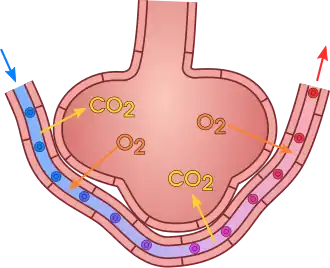

Los pulmones son los órganos en los cuales la sangre recibe oxígeno procedente del aire inspirado y se desprende del dióxido de carbono, el cual pasa al aire espirado. Este intercambio, se produce mediante difusión simple de los gases gracias a la diferencia de presiones parciales de oxígeno y dióxido de carbono entre la sangre y los alvéolos.

El pulmón recibe la sangre procedente del ventrículo derecho a través de la arteria pulmonar. La arteria pulmonar se divide en dos ramas una para el pulmón derecho y otra para el izquierdo, las cuales se ramifican progresivamente siguiendo un trayecto paralelo al de las vías respiratorias. El sistema venoso es más variable y puede disponerse en diferentes trayectos, pero finalmente las cuatro venas pulmonares, dos procedentes del pulmón derecho y dos del izquierdo, desembocan en la aurícula izquierda. Hay que tener en cuenta que la circulación pulmonar presenta una peculiaridad con respecto al resto de la circulación sistémica, puesto que las arterias pulmonares son las únicas arterias del organismo que transportan sangre desoxigenada, mientras que las venas pulmonares, tras el intercambio gaseoso en los alvéolos, aportan sangre oxigenada hacia la aurícula izquierda, el intercambio entre oxígeno y dióxido de carbono se realiza mediante difusión entre la luz de los alveolos pulmonares y los capilares sanguíneos.[4]

La función principal de los pulmones es realizar el intercambio gaseoso con la sangre. En los alvéolos se produce el paso de oxígeno desde el aire a la sangre y el paso de dióxido de carbono desde la sangre al aire. Este intercambio ocurre por difusión simple debido a la diferencia de presiones parciales de oxígeno y dióxido de carbono entre la sangre y los alvéolos. En los capilares pulmonares que rodean a los alvéolos tiene lugar el intercambio gaseoso, de tal forma que la hemoglobina se desprende de una molécula de dióxido de carbono y toma la de oxígeno. Todas las células del cuerpo utilizan este oxígeno para realizar la oxidación de glucosa generando así la energía necesaria para que cada una de ellas continúe funcionando. La oxidación ocurre en un orgánulo de las células denominado mitocondria donde se genera como subproducto dióxido de carbono.[6]

Para que se produzca el intercambio de gases es necesario que estos atraviesen la membrana respiratoria, la cual está formada por cuatro capas:

- La pared del alveolo, formada por los neumocitos tipos I y II junto a macrófagos.[4]

- Membrana basal epitelial ubicada por debajo de la pared alveolar.

- Membrana basal del capilar.

- Endotelio del capilar, es decir la capa de células que forma la pared del vaso capilar.

El conjunto de esta cuatro capas es fínísimo y solo tiene un espesor de 0.5 micras, es decir la mitad de una milésisma de milímetro. Esta disposición permite que el intercambio de gases sea muy eficaz.